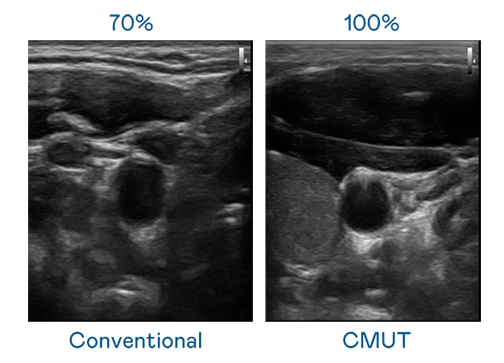

CMUT 技术是一种用电容式微机电元件来产生超音波讯号的技术。与传统 PZT 压电式技术相比,CMUT 频宽增加 30%,更宽频的超音波讯号让影像解析度大幅提升,是实现高影像品质医疗超音波扫描、促进精准医疗发展的关键技术。

超音波影像的解析度高低,首先取决于探头能发出的讯号频宽。J9九游会 CMUT 可提供高清晰的超音波讯号,提供高频宽、高灵敏度、影像纹理细节更高的超音波影像,协助医护人员缩短影像判读时间及利用精准的医疗影像进行诊断。